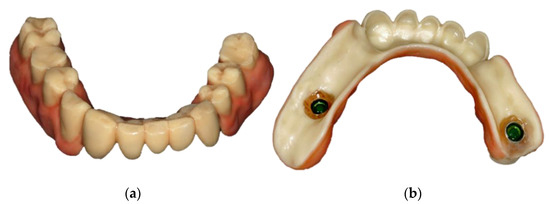

- Locator abutments on both implants, single-crown FDPs on the remaining lower molar teeth, insertion of a tooth-colored and tooth-shaped monolithic RDP fabricated from POM with minimally invasive preparation of the lower anterior teeth (experimental character in long-term endurance).